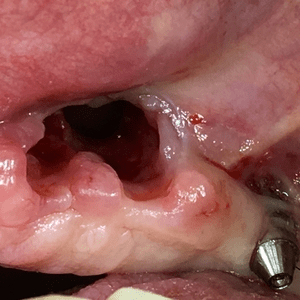

La chirurgia orale comprende tutti gli interventi eseguibili in anestesia locale che possono essere effettuati nell’ambito del cavo orale. Sono pertanto di pertinenza della chirurgia orale le avulsioni dentarie di elementi non più trattabili, le avulsioni dei denti inclusi e/o malposizionati, il trattamento di ascessi, amputazioni di apici radicolari (apicectomie) e la rimozione di cisti.